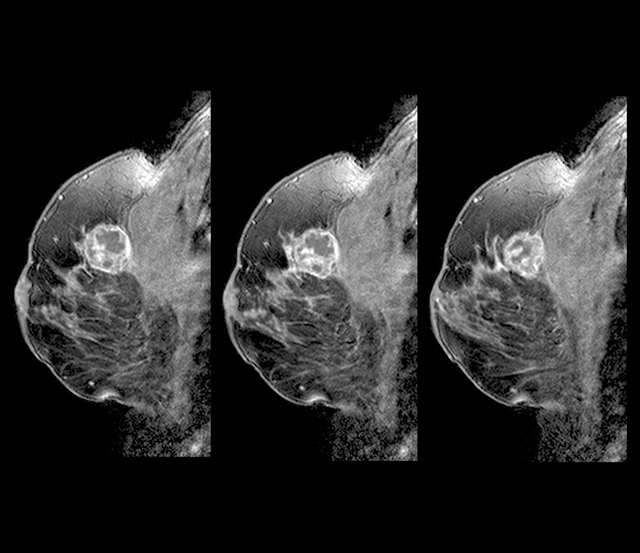

유방암 초기증상 - 덩어리 또는 멍울

유방암을 알아차리는 가장 일반적인 방법은 유방에 덩어리 또는 만져지는 덩어리가 만져지는 것입니다. 멍울은 이전에 본 적 없는 신비한 덩어리이며, 악성이라면 단단하고 고정되어 움직이지 않으며 모양이 불규칙합니다. 모든 멍울이 악성은 아니며 양성일 수도 있으므로 의사와 정기적으로 검진을 받는 것이 중요하므로 이러한 유방암 초기증상을 그냥 지나치지 마시기 바랍니다.